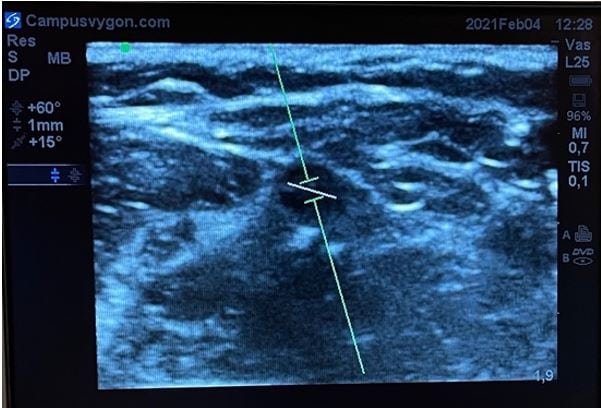

Manteniendo la exploración en modo B, activamos el modo doppler espectral. A continuación, colocamos el volumen de muestra (identificado como dos líneas paralelas y perpendiculares al eje del haz de ultrasonidos) en el interior del vaso que se pretende estudiar. El tamaño del volumen de muestra debe ser proporcional al calibre del vaso a estudiar.

Angulamos el transductor entre 30 a 60º o bien hacia la parte distal del cuerpo (hacia la mano) o hacia la parte proximal (hacia la cabeza), y por último volvemos a activar el modo doppler espectral para que comience el análisis de velocidades.

Si el espectro de velocidades se sitúa sobre la línea base significará que el flujo del vaso sanguíneo estudiado se dirige hacia el transductor. Por el contrario, si el espectro de velocidades se sitúa por debajo de la línea de base, significará que el flujo del vaso sanguíneo estudiado se alejará del transductor.

Además del sentido de la sangre, la morfología del espectro nos informará del carácter del flujo del vaso estudiado. Así, si el flujo es pulsátil, habitualmente se tratará de un vaso arterial. Mientras que si el flujo es continuo o poco pulsátil, habitualmente se tratará de un vaso venoso.